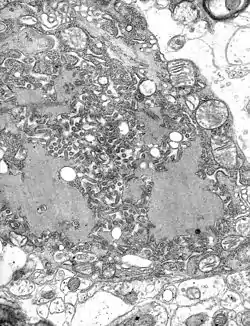

Rendering of the rabies virus An electron microscope image of the rabies virus

An electron microscope image of the rabies virus TEM micrograph with numerous rabies virions (small, dark grey, rodlike particles) and Negri bodies (the larger pathognomonic cellular inclusions of rabies infection)

The rabies virus is the type species of the Lyssavirus genus, in the family Rhabdoviridae, order Mononegavirales. Lyssavirions have helical symmetry, with a length of about 180 nm and a cross-section of about 75 nm.[33] These virions are enveloped and have a single-stranded RNA genome with negative sense. The genetic information is packed as a ribonucleoprotein complex in which RNA is tightly bound by the viral nucleoprotein. The RNA genome of the virus encodes five genes whose order is highly conserved: nucleoprotein (N), phosphoprotein (P), matrix protein (M), glycoprotein (G), and the viral RNA polymerase (L).[34]

To enter cells, trimeric spikes on the exterior of the membrane of the virus interact with a specific cell receptor, the most likely one being the acetylcholine receptor. The cellular membrane pinches in a procession known as pinocytosis and allows entry of the virus into the cell by way of an endosome. The virus then uses the acidic environment, which is necessary, of that endosome and binds to its membrane simultaneously, releasing its five proteins and single-strand RNA into the cytoplasm.[35]

Once within a muscle or nerve cell, the virus undergoes replication. The L protein then transcribes five mRNA strands and a positive strand of RNA all from the original negative strand RNA using free nucleotides in the cytoplasm. These five mRNA strands are then translated into their corresponding proteins (P, L, N, G and M proteins) at free ribosomes in the cytoplasm. Some proteins require post-translational modifications. For example, the G protein travels through the rough endoplasmic reticulum, where it undergoes further folding, and is then transported to the Golgi apparatus, where a sugar group is added to it (glycosylation).[35]

When there are enough viral proteins, the viral polymerase will begin to synthesize new negative strands of RNA from the template of the positive-strand RNA. These negative strands will then form complexes with the N, P, L and M proteins and then travel to the inner membrane of the cell, where a G protein has embedded itself in the membrane. The G protein then coils around the N-P-L-M complex of proteins taking some of the host cell membrane with it, which will form the new outer envelope of the virus particle. The virus then buds from the cell.[35]